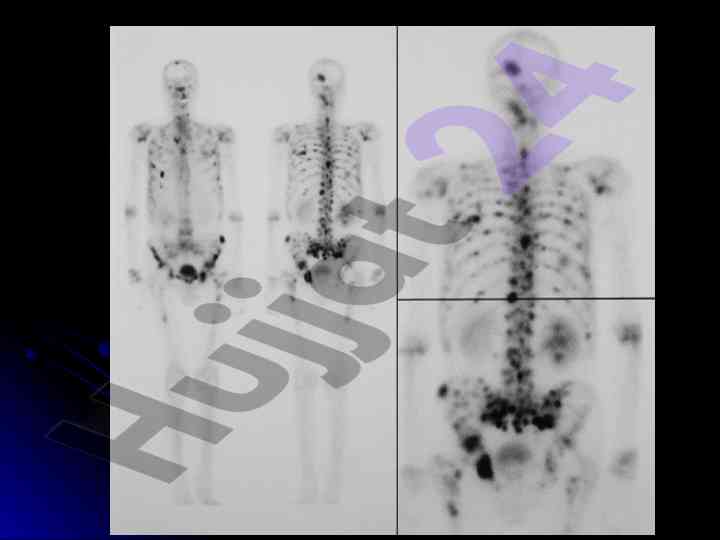

Рентгенография, ультрасонография ва сцинтиграфия усуллари тянч-харакат тизими касалликлари диагностикасида муhim аҳамиятга эга. Инсон организмининг юз бериши мумкин бўлган ўзгаришларни аниқлашда муҳим рол ўйнайди.